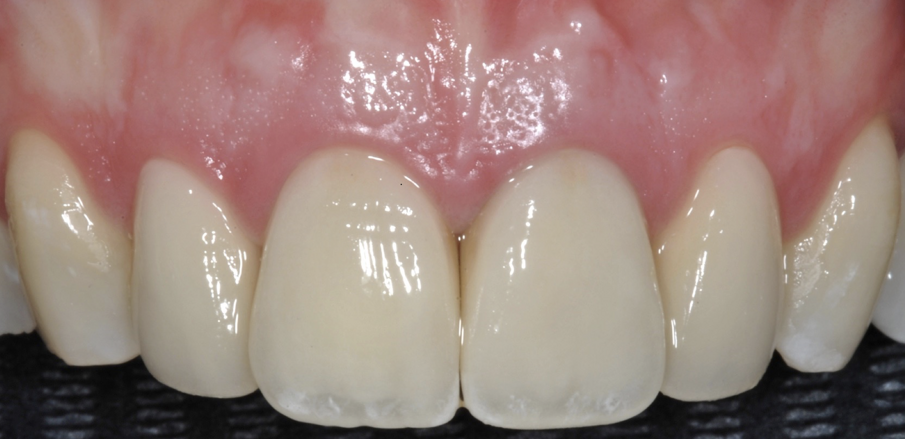

Fig. 14-16 - Il caso ultimato.